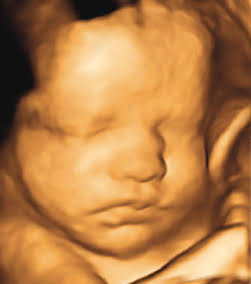

ECOGRAFÍAS DE EMBARAZO

¡Bienvendio a Multilab, tu destino confiable para servicios de ecografía de embarazo!

Descubre la magia de la maternidad a través de nuestras cuatro opciones especializadas de ecografías de embarazo. Con equipos de última generación y profesionales altamente capacitados, te ofrecemos una excelente experiencia.

Ecografía Obstétrica 6D Conocer al bebé en 6D 24 a 32 Ver